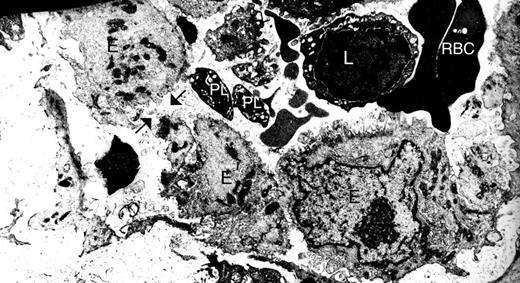

For this study, we aimed to examine platelets in a context where increased vasculature permeability and inflammation are present. Gaps are found between endothelial cells in the synovial vasculature from patients with RA,10 and our electron microscopic analyses of synovial tissues from these patients also reveal platelets in the vicinity of these gaps10 (Figure 1). Thus, autoimmune inflammatory arthritis appeared to us as an ideal condition to investigate the role of platelets in the context of enhanced vasculature permeability.

Gaps are present between endothelial cells in the synovium vasculature from patients with RA. Synovium from RA patients was scrutinized by electron microscopy. Black arrows indicate one gap between endothelial cells. E indicates endothelial cells; PL, platelets; L, lymphocytes; and RBC, red blood cells. Original magnification ×48 400.